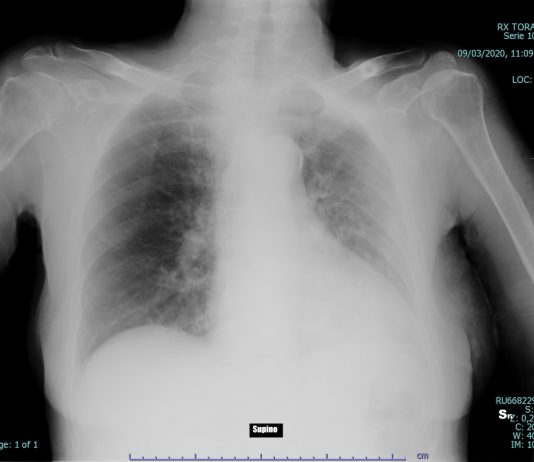

82-years-old female patient, admitted to the ED with dyspnea and fever for 7 days. Medical history: HTA and kidney cancer. Blood test: C-PR 106,93 (< 5); ESR 45 (<15);...